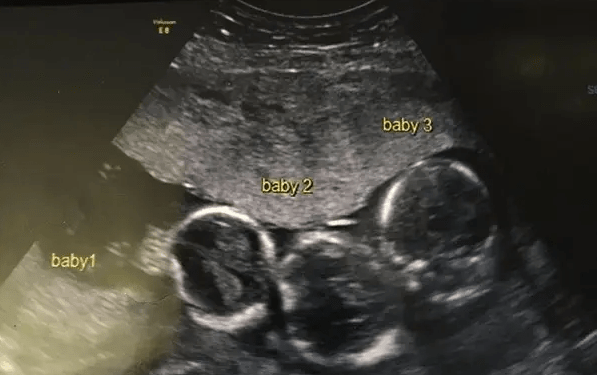

Trojčatá bez genetickej predispozície

Ultrazvuk ukázal, že Becki čaká trojičky. A nielen to – všetky tri deti boli identické. Lekári potvrdili, že ide o výnimočne zriedkavý prípad. Pravdepodobnosť vzniku identických trojičiek sa pohybuje okolo 1 ku 200 miliónom. V rodine sa žiadne viacnásobné tehotenstvo nevyskytovalo, takže šok bol o to väčší.